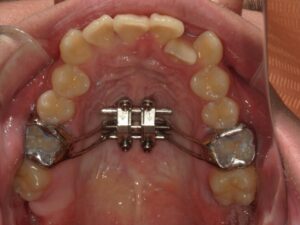

MSEとは、上顎を広げるための装置です。

正式には「Maxillary Skeletal Expander)」といいます。

・真ん中にネジ(スクリュー)があり、それを回すことで拡大力を発生させます。

・装置の基部がミニスクリュー(4本程度)で上顎骨(口蓋骨)に直接固定されます。

・骨に固定するため、歯の傾斜を抑えて上顎骨そのものを広げることができます。